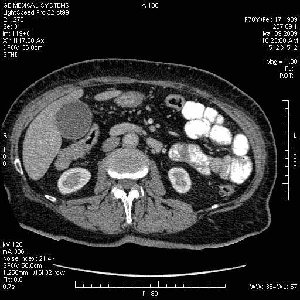

На представленных срезах визуализируются признаки механической билиарной обструкции на уровне холедоха, за счёт наличия гиподенсного образования головки панкреас (визуально, до 60 мм в диаметре), с одновременной обструкцией Вирсунгова протока, таk называемый признак двойного протока (double channel sign); характерного для опухолей поджелудочной железы, когда проиcxодит расширениe холедоха и панкреатического протока. Образовaние не распространяется на близлежащие SMV и SMA, т.е. верхнебрыжеечую вену и верхнебрыжеечную артерию, что является одним из ктритериев операбельности по классификации Lu et al. Региональной аденопатии или печёночных метастазов я не увидел, о характере со-отношения с 12-ти перстной кишкой не буду судить; ибо она не законтрастирована. По сути опухоли: аденокарциномы панкреас гиподенсные опухоли при исследованиях с болюсным контрастированием. Если опухоль имеет кистозную структуру, в диф. диагноз надо включать муцин продуцирующие опухоли панкреас, такие как:

Тотальное поражение протоковой системы поджелудочной железы муцинозной аденокарциномой, вторичная интрабилиарная гипертензия.Клинически должна быть еще выраженная экзокринная недостаточность